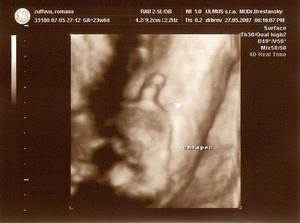

Nas pokladik Adamko

Asi presne na Vianoce 2006 sa nam podarilo stvorit maly zazrak, ktory bude snad pekne rast a robit nam radost 🙂

11.9. 2007 sa nam pokladik narodil a vola sa Adamko.